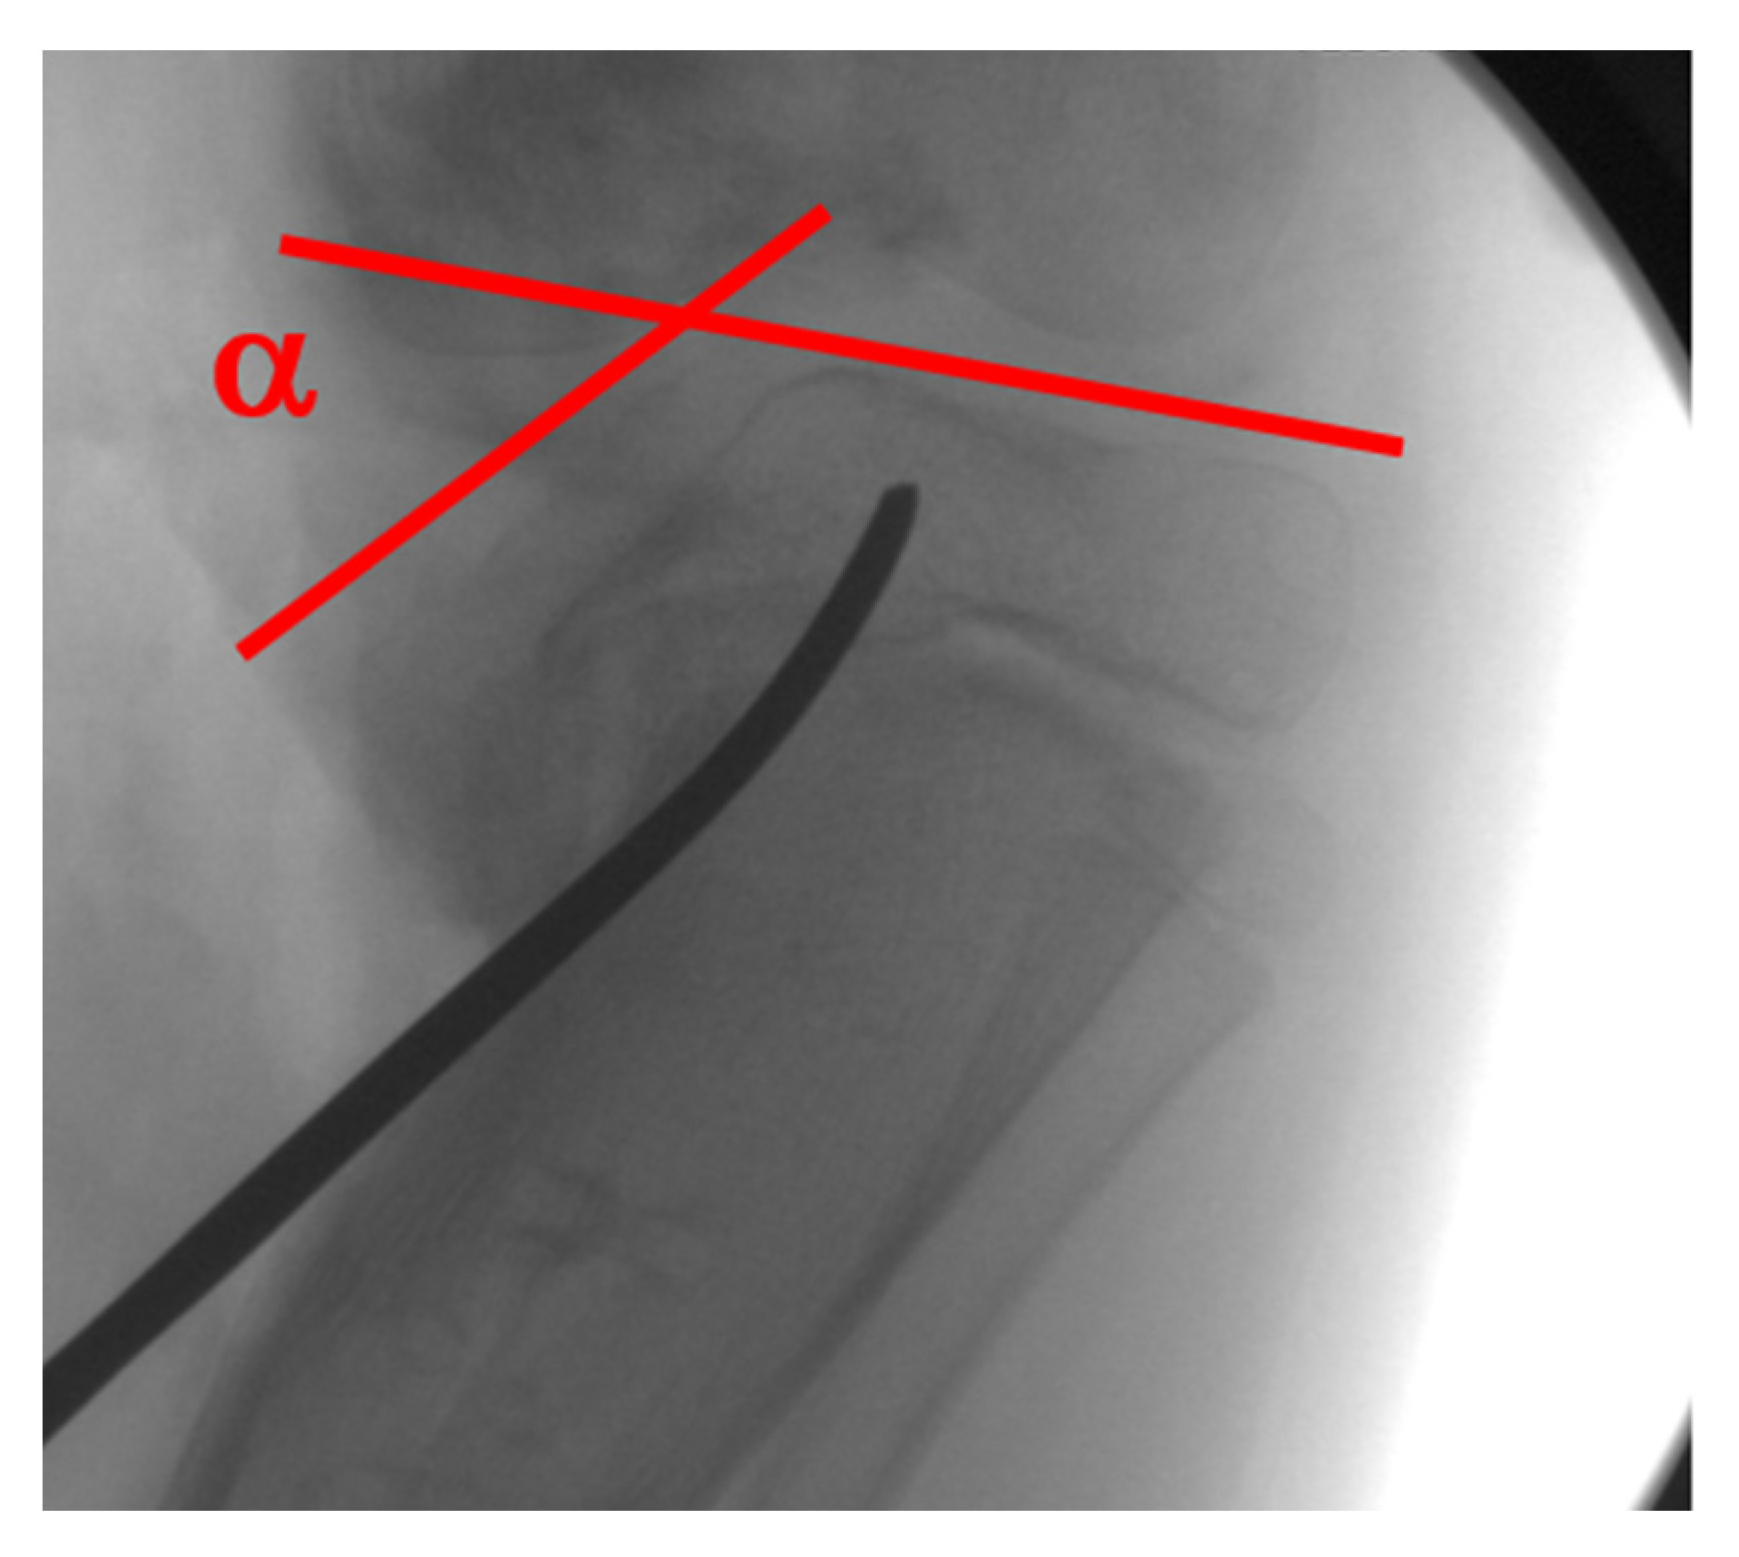

5. Radiographic Analysis